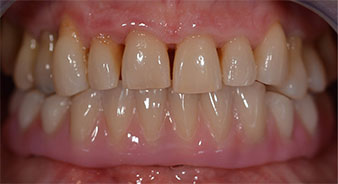

Die 64-jährige Patientin wurde mit einer Unterkiefer-Restbezahnung 38, 33 und 43 und einer klammerbefestigten Interimsprothese im Unterkiefer vorstellig (Abb. 1 und 2).

Die notwendige parodontologische Behandlung und Extraktion im Oberkiefer sollte zu einem späteren Zeitpunkt erfolgen, da die Patientin Lehrerin ist und zu dem Zeitpunkt mit Abiturprüfungen beschäftigt war. Sie konnte weder essen noch adäquat sprechen, da die Interimsprothese sehr häufig und bei der kleinsten Belastung brach.